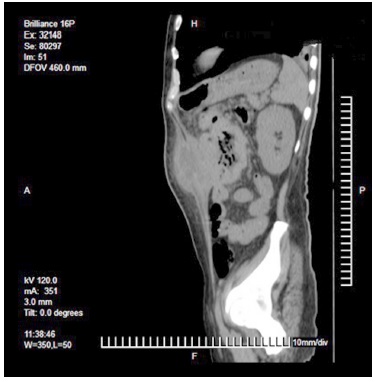

Laboratorios a su ingreso: hemoglobina 9,3 g/dL, hematocrito 29,6 %, plaquetas 574 x 109/L y albumina 1,6 g/dL, resto dentro de parámetros normales. Se realizó una tomografía abdominal que reportó un tumor dependiente del colon transverso con invasión a pared abdominal y formación de absceso (Figura 1, 2 y 3). Con el paciente en estado séptico, se decide el drenaje y la exploración quirúrgica previa estabilización.

La utilidad de la colonoscopia y la biopsia por este medio, han sido las herramientas de tamizaje y diagnóstico temprano [13-15], sin embargo, esta herramienta tiene sus limitaciones al estar confinada a la luz intestinal, así como un riesgo de error en la toma de biopsia en caso de un tumor heterogéneo. En los casos de absceso de pared abdominal, independientemente de su origen, la tomografía juega un papel crucial en el diagnóstico [10,16].